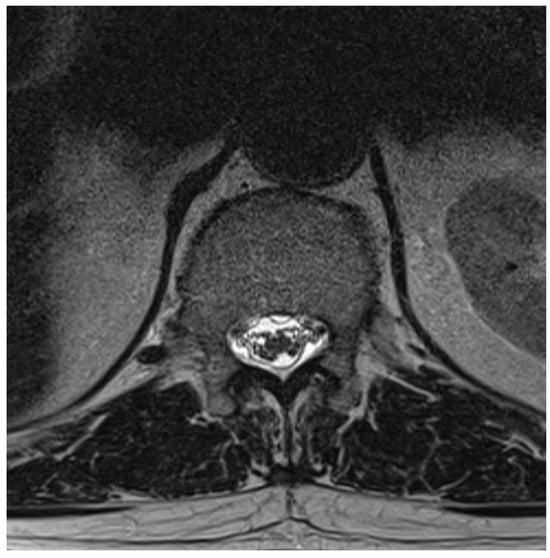

Among the 722 punctures, complications occurred in four cases (0.6%), see Table 3. Three of these complications arose after the first administration and one after the second. Reported complications included one case of post-puncture aggravation of pain, and one case of post-puncture headache. Both cases were managed conservatively using analgesics. In one case, shortness of breath occurred. In this patient, a cardiopulmonary event was ruled out, which required performing blood sampling as well as a CT-angiography of the pulmonary arteries. In another case, an intracranial subdural hygroma occurred, see Figure 2. No neurological deficits occurred, but due to persistent headache, an MRI scan was performed which revealed the diagnosis. The patient was readmitted for inpatient treatment for another 5 days 1 month after initial puncture. An MRI scan of the lumbar scan revealed epidural accumulations of cerebrospinal fluid at the thoracolumbar junction (Figure 3). Bed rest was ordered for 3 days. 2 days after readmission, a CT-guided lumbar blood patch was performed at the level L2 with 35 mL of blood, and oral analgesics were administered. The patient was discharged after five days. At subsequent follow-up visits, the patient reported no further headaches, and an MRI performed six weeks later demonstrated the complete resolution of the epidural cerebrospinal fluid collections (Figure 4).

Figure 3. Axial T2-weighted MRI at L1, showing epidural cerebrospinal fluid accumulation both ventral and dorsal to the thecal sac.